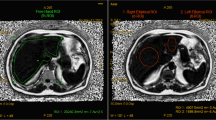

In general, we found that the right lobe had a greater degree of fat deposition than the left lobe after using free-drawn-PDFF-2 method (p < 0.001) (Table 1). The mean difference in fat percentage, estimated by free-drawn-PDFF-2 between the two lobes, was 0.93 % (range 0.01–5.01 %). The difference in fat percentage between the two lobes was statistically significant in both the steatotic and non-steatotic groups (p < 0.001) (Fig. 4). There were five cases of discrepancy in which the estimated free-drawn-PDFF-2 was lower than 5.56 % on one side of the liver and higher than 5.56 % on the remaining side (Fig. 5).

An 18-year-old female with hepatic steatosis: In-phase (a), opposed-phase (b) and PDFF fat percentage map (c) show uneven fatty distribution. A free-drawn region-of-interest (ROI) was placed at the umbilical portion of the left portal vein as representative image of “free-drawn-PDFF” (d), the free-drawn ROI of the right lobe (e), and the free-drawn ROI of the left lobe (f) were placed at the same level as representative images of “free-drawn-PDFF-2”. Fat fractions (FF) of both lobes, right lobe, left lobe, and SVS were 7.5, 9.8, 6.1, and 15.7 %, respectively

The findings of our study were similar to those cited above regarding heterogeneity of liver fat content. The fat percentage of the right lobe, as determined by free-drawn–PDFF-2, was higher than that of the left lobe in both the steatotic and non-steatotic groups (p < 0.001). Voxels used in SVS were usually located in segment VI or VII of the right lobe. Since the right lobe had a relatively higher fat content as compared to the left lobe, SVS results may have had a tendency to overestimate the fat content of the liver, particularly if the difference between the two lobes was large. There were five discrepant cases in our study in which the fat content of one side of the liver was high enough to qualify as steatotic while the other side did not meet such criteria. Among the discrepant cases, four had steatosis only in the right lobe and one had steatosis only in the left lobe. This asymmetry could account for possible over- or underestimation when fat percentage is estimated in only one side of the liver. Furthermore, in cases of severely asymmetrical fatty infiltration, SVS may lead to erroneous results because this technique reflects only fat deposition in a single voxel (Fig. 5).